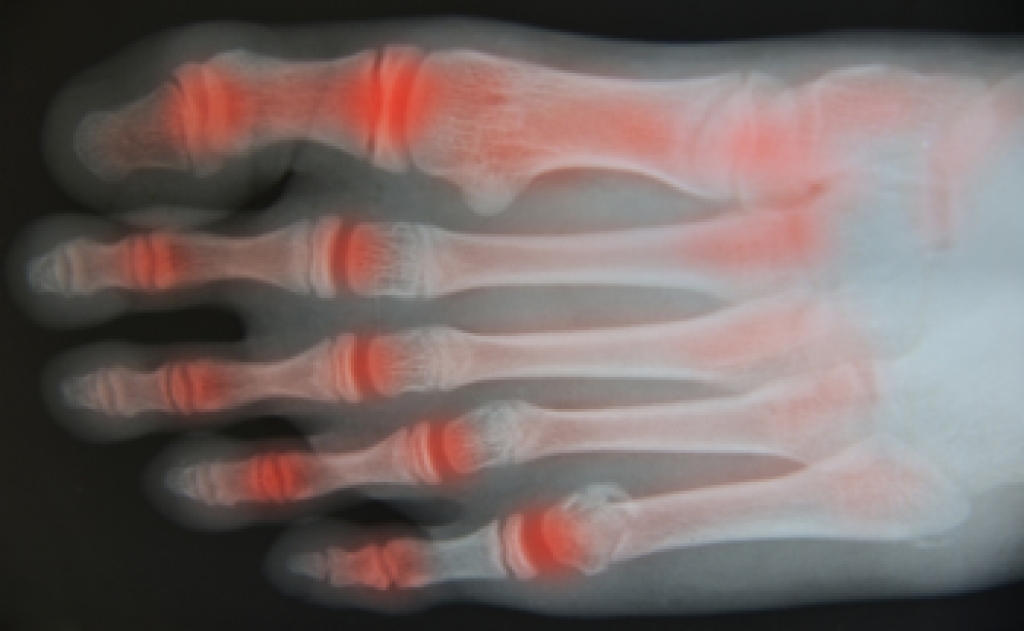

- Arthritis (such as Gout, Rheumatoid, and Osteoarthritis)

To figure out the cause of foot pain, podiatrists utilize several different methods. This can range from simple visual inspections and sensation tests to X-rays and MRI scans. Prior medical history, family medical history, and any recent physical traumatic events will all be taken into consideration for a proper diagnosis.